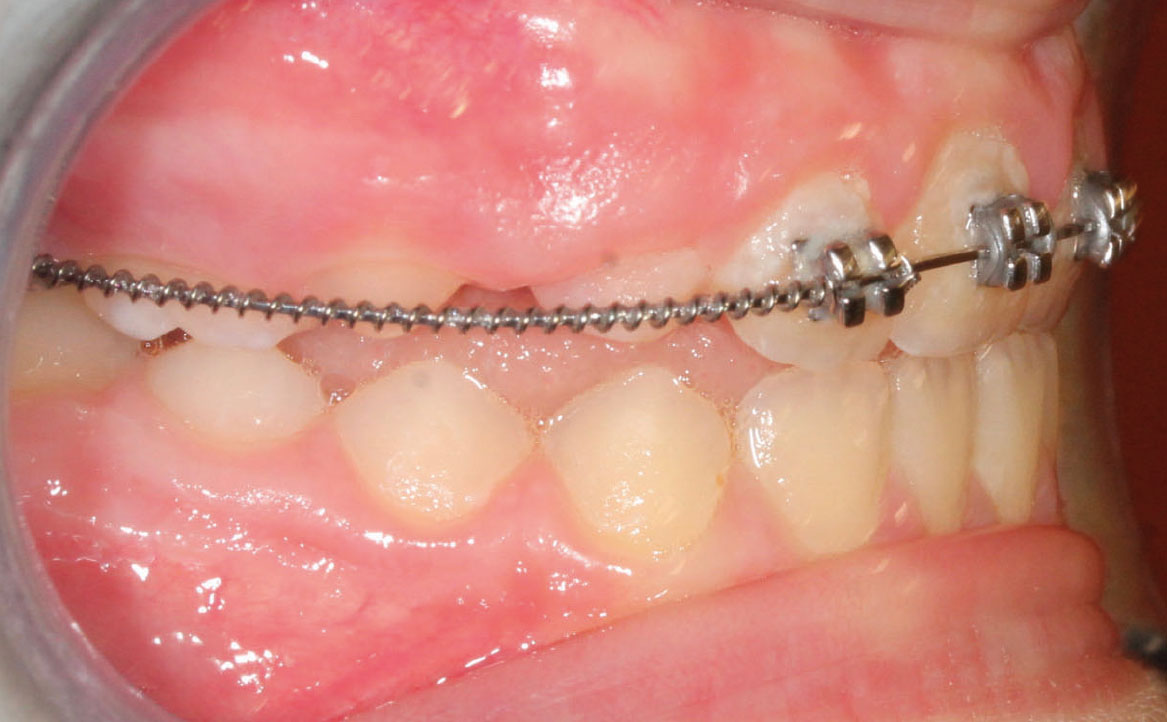

Fig. 8A Terapia intercettiva con REP e bandaggio parziale superiore.

Bandaggio e sequenza archi

A tre mesi dalla cementazione dell’ERP si programma il bandaggio parziale superiore da 12 a 22 (Mini Master, prescrizione MBT, slot 22×28, American orthodontics) posizionando in maniera strategica i bk su 12 e 22, per il controllo del tip ed evitare interferenza con il tragitto eruttivo di 13 e 23. Sono state posizionate delle open coil attive e arco 016 Tanzo (fig. 8).

Al controllo successivo, a distanza di un mese, viene riattivata l’open coil e aumentati i rialzi occlusali già presenti.

A tre mesi dal bandaggio parziale viene inserito arco 016×22 Tanzo.